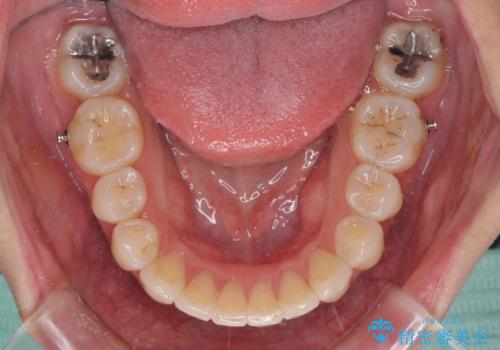

- 抜歯矯正の後戻りで前歯が突出してきていることを気にして来院された患者様です。

口元の突出感を改善するにあたり、抜歯矯正は行うことができないため、奥歯の後方移動とIPR(歯と歯の間を削る)により達成することとしました。

再度後戻りしたときに対応しやすいよう、インビザラインにて矯正治療を行うこととしました。

しっかりと装着時間を守り、ゴムかけにも協力していただいたので、口元を引っ込めることができました。